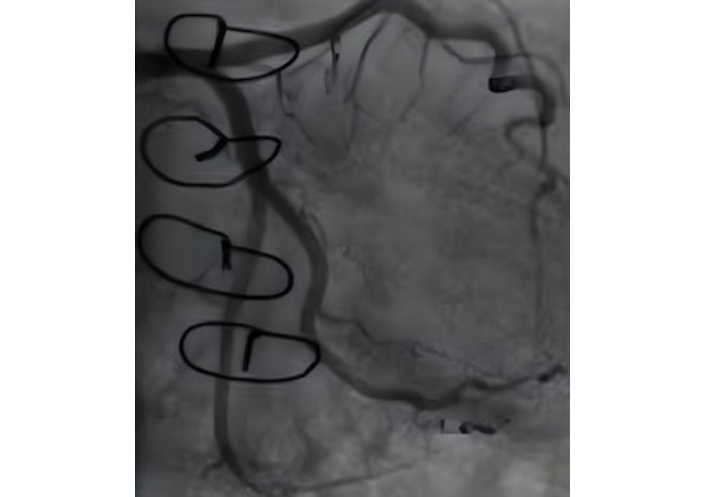

A TTE evaluation performed three months later did not report the mass seen on CXR as a possible pseudoaneurysm (Figure 4). The mass on the left side became more prominent on CXR (Figure 5), nineteen months later. A thoracic CT scan revealed a giant pseudoaneurysm on the posterior wall of LV which was 10 cm × 7 cm in size (Figure 6). The patient was urgently transferred to our center for definitive management, where a coronary angiography (CA) was performed. CA showed normal coronary anatomy (Figures 7 and 8), but left ventriculography confirmed the diagnosis: leakage of contrast medium into the pseudoaneurysm sac was clearly observed (Figures 9 and 10).

Ventricular angiography has been traditionally considered the “gold standard” for the diagnosis of pseudoaneurysms. Currently, this diagnostic technique is only applied in a limited number of cases due to its time-consuming nature and the risk of pseudoaneurysm rupture [8]. In this case, besides showing normal coronary anatomy, it also allowed us to clearly measure the pseudoaneurysm size and provided information about the complete filling of the sac and the absence of thrombi. Cardiac CT or magnetic resonance image (MRI) is also the most definitive test, and the information they provide is essential for early diagnosis and appropriate treatment planning [9, 10].